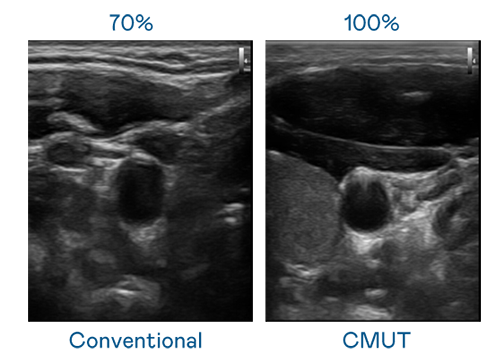

CMUT 技术是一种用电容式微机电元件来产生超音波讯号的技术。与传统 PZT 压电式技术相比,CMUT 频宽增加 30%,更宽频的超音波讯号让影像解析度大幅提升,是实现高影像品质医疗超音波扫描、促进精准医疗发展的关键技术。

大频宽带来超清晰影像

超音波影像的解析度高低,首先取决于探头能发出的讯号频宽。HJC黄金城 CMUT 可提供高清晰的超音波讯号,提供高频宽、高灵敏度、影像纹理细节更高的超音波影像,协助医护人员缩短影像判读时间及利用精准的医疗影像进行诊断。